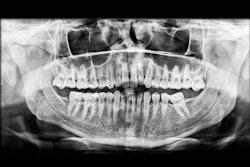

The oral surgeon ordered a cone-beam CT (CBCT) exam. Click images below to enlarge. In order: reformatted panoramic radiograph and cropped image of the area of interest, coronal view of the posterior right mandible (the inferior alveolar canal in red), and 3D reconstructed image of the posterior right mandible.

Figure 1: Reformatted and cropped panoramic film. All images courtesy of Dr. Juan F. Yepes.

Figure 2: Reformatted and cropped panoramic film.

There is a hypodense lesion (radiolucent) that is well-defined, well-corticated, oval in shape, 8 x 6 mm, located at the posterior right mandible, and distal to tooth #32. The lesion is located below the inferior alveolar canal. No expansion is observed in the cross-sectional views. No calcifications are observed inside the lesion.

From the radiographic perspective, Stafne bone defects are radiolucent lesions, well-defined and well-corticated, oval in shape, and located below the inferior alveolar canal. No expansion is usually observed in the coronal views.